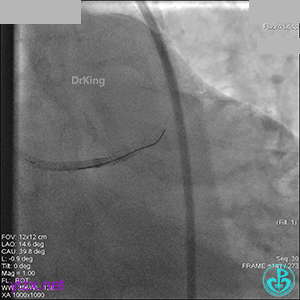

1周后再次上台,右冠脉3级血流,3段局限性严重狭窄,内膜模糊,应该是上次操作夹层遗留下的血肿。

先处理前降支开口严重狭窄并顺利植入前降支到左主干支架。